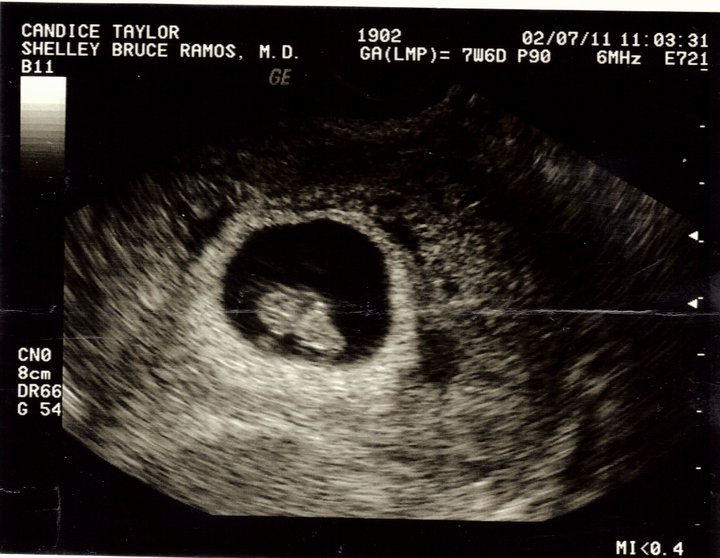

So the big news if you didn't know by now is that John and I are expecting a baby September 20. We are both super excited!! Here are some of the sonogram pictures.

7 Weeks 6 Days